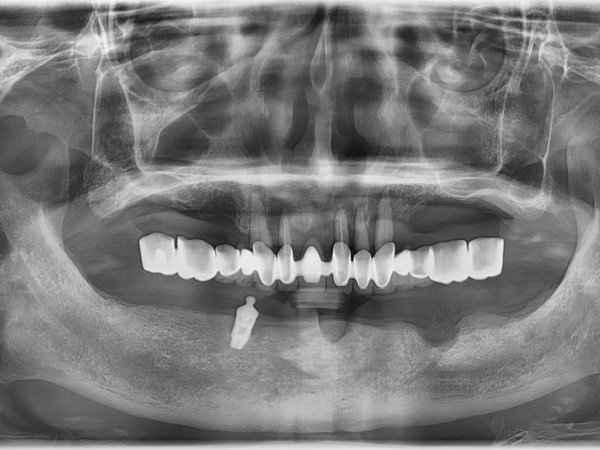

디지털 임플란트

어르신 임플란트